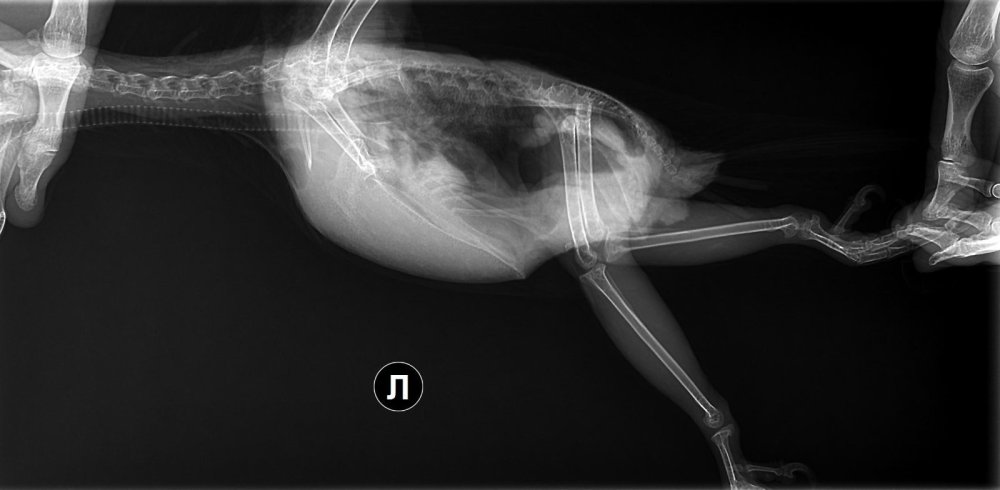

Здравствуйте! Венесуэльский амазон Пол: Самец (проводили ДНК тест по перу) Возраст: предположительно, 13 лет Ранее не болел, взят из дикой природы примерно в 2 года, живет у нас 10 лет. Вес: 0.435 Первые симптомы обнаружились 17 декабря: у попугая вечером ослабли лапы, он не мог нормально на них стоять, передвигаться, приходилось его подстраховывать и взять на ручки. В течение получаса пребывал в таком состоянии и не издавал особо никаких звуков, не реагировал, будто "был не здесь", не могу иначе назвать, к сожалению. С этого момента раз в несколько дней такие ситуации повторяются, но он восстанавливается гораздо быстрее. Такое чаще всего ближе к вечеру, реже - в первой половине дня. Лапки ослабевают, но при этом он уже остается в сознании, реагирует. 19 декабря были на приеме у врача, сделали рентген в двух проекциях, на нём ничего не обнаружили. По анализам: повышен холестерин (13.5), триглицериды (2.5), калий (2.7), моноциты (8), базофилы (4). Понижен фосфор неорганический (0.63). Препараты: с 20 декабря давали неболинвет 0.4мл 2 р\д в течение 7 дней с 23 декабря даем легалон 70 (по 1\2 капсулы в корм 2 р\д) и гептрал (1/4 таблетки на 1 мл воды -> по 0.3мл 2р\д на кашу или фрукты, которые сразу же он ест) Ограничили по рекомендации врача рацион - орехи редко, больше овощей, фруктов и зелени, замоченный корм. По содержанию все соответствует - разные жердочки, большая клетка, искусственное освещение по расписанию Сегодня (02.01.2026) была слабость, длилась дольше, чем обычно (минут 25), но при этом он никак не мог успокоиться и посидеть. Заметили, что клюв и сам попугай теплее, чем обычно, даже чуть горячий. Подскажите, пожалуйста, что можно еще сделать, на что обратить внимание? Нам предлагал еще другой врач нейромультивит и ноотропы, но мы пока придерживаемся того лечения, которое описал выше. Приложу рентгеновские снимки. -